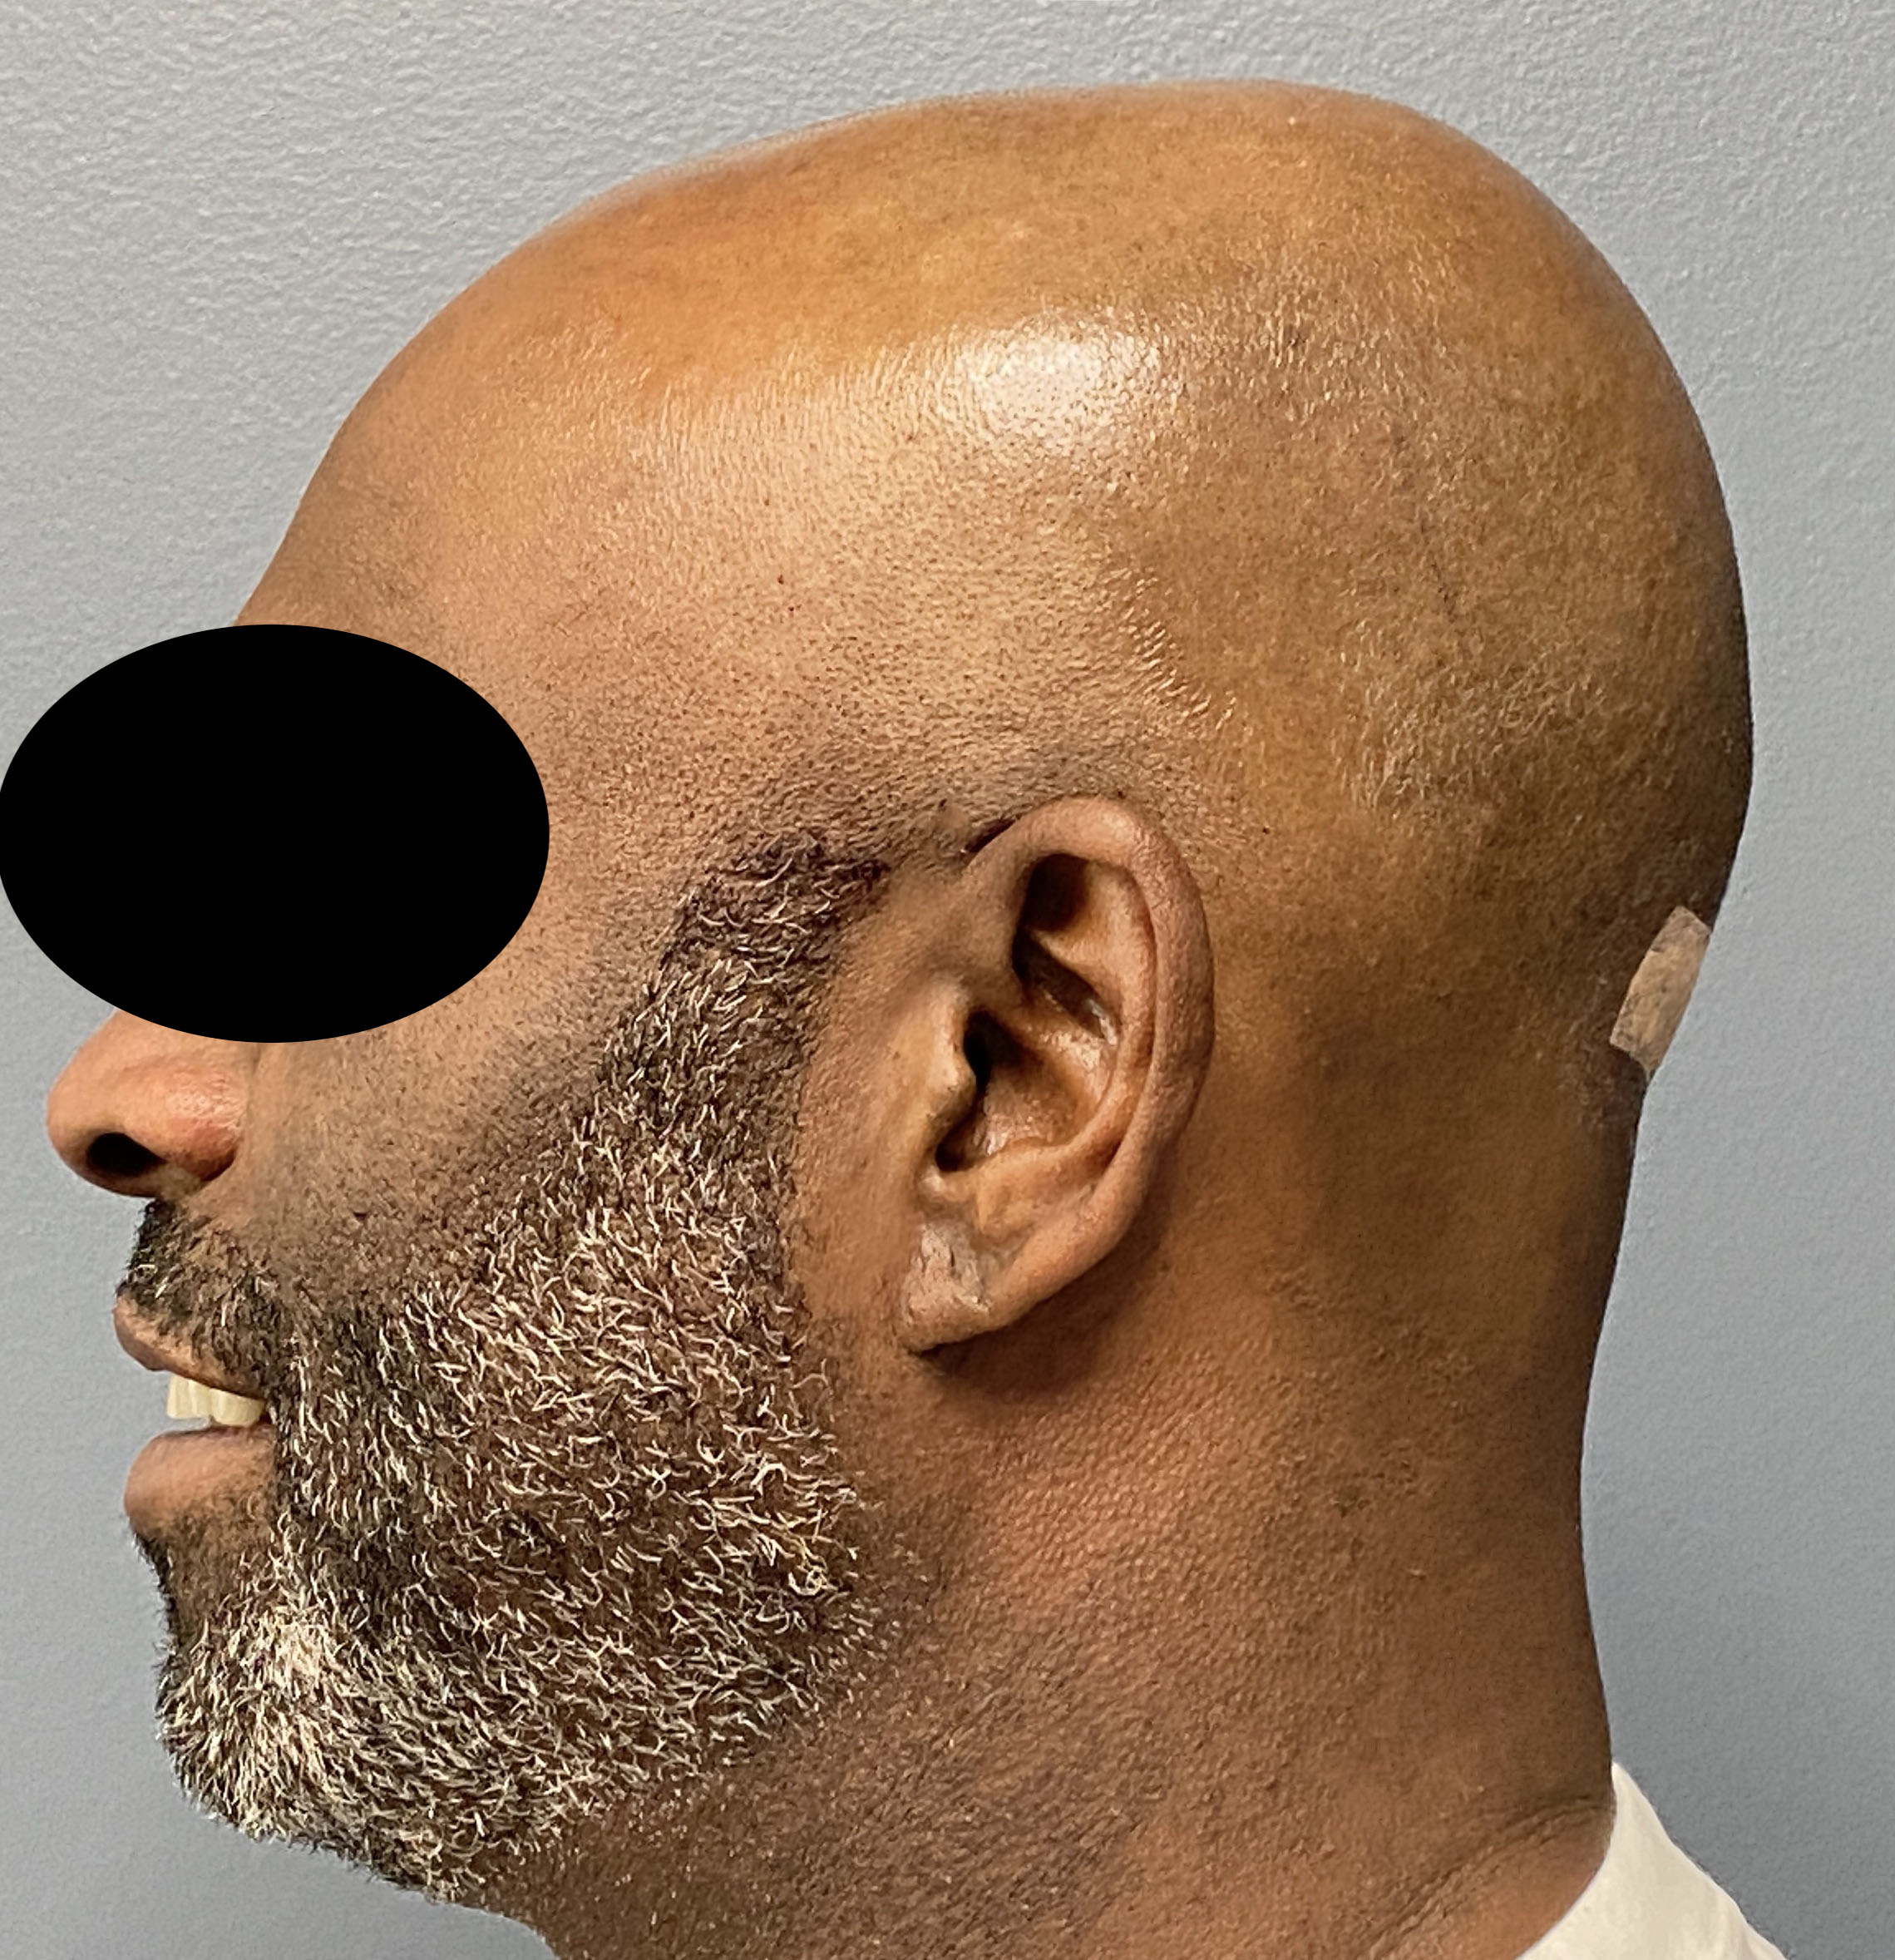

Patient 129

Desire for reduced width/convexity on the sides of his head.

Head narrowing using a temporal muscle transposition technique seen one day postop. He also had an concurrent occipital skull reduction done hence the tape over his incision.

Desire for reduced width/convexity on the sides of his head.

Head narrowing using a temporal muscle transposition technique seen one day postop. He also had an concurrent occipital skull reduction done hence the tape over his incision.